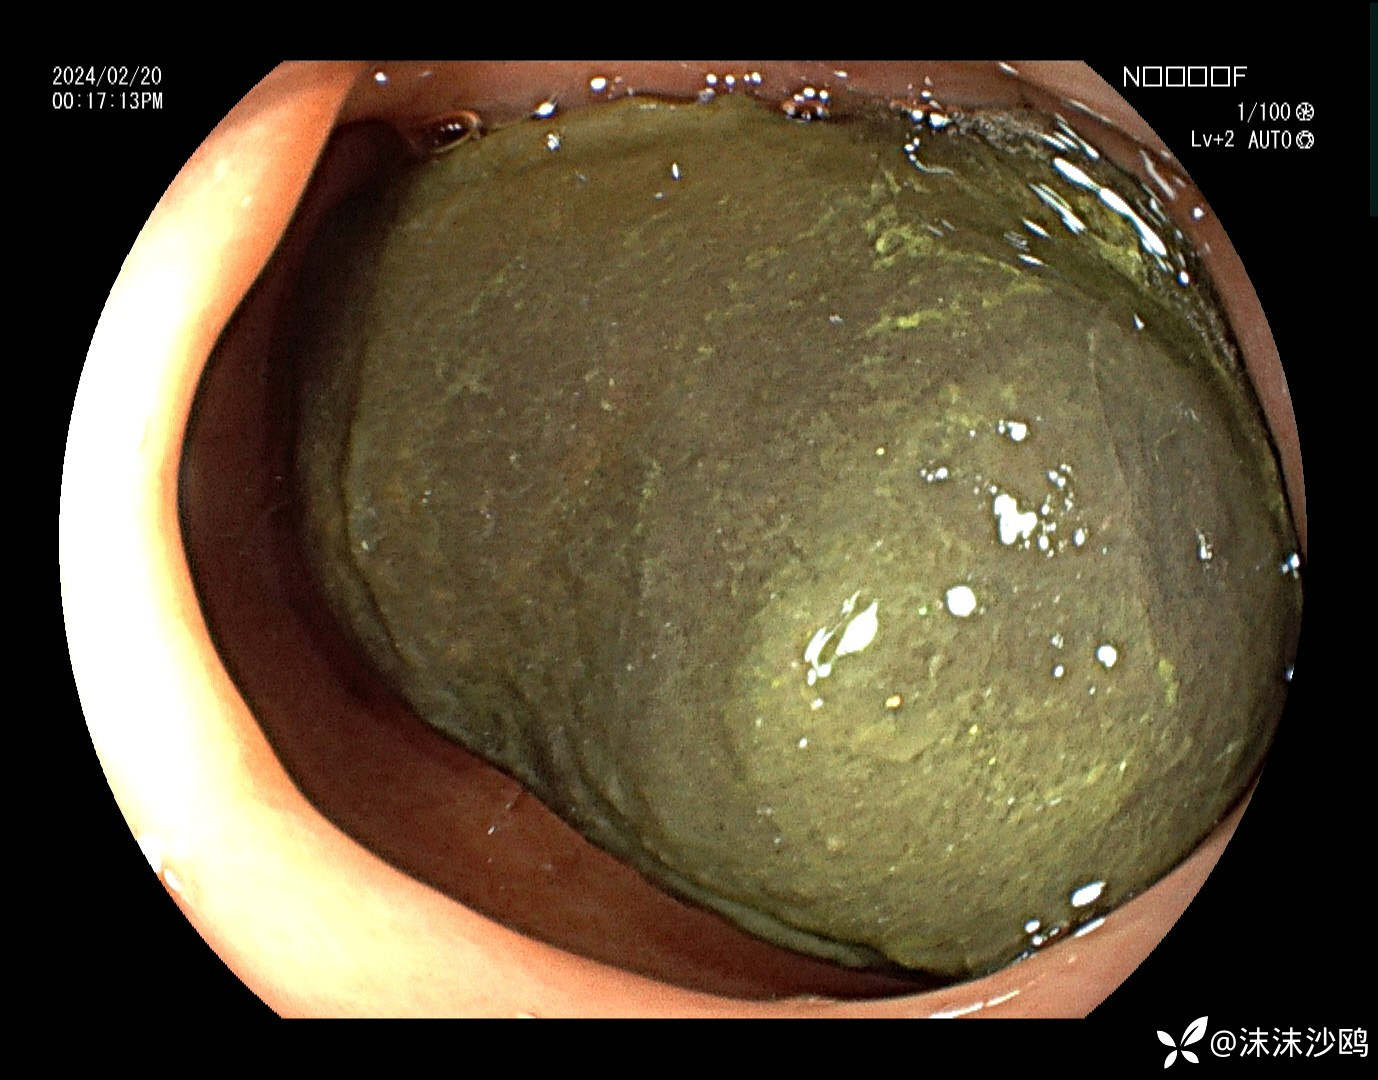

中年男子,腹痛就诊,行普通肠镜检查。胃腔内见大量胃液潴留,吸引了三四百毫升。进到幽门有了发现。

巨大异物嵌顿在球部,考虑胃石导致梗阻。询问病史,就是吃了几个车厘子,没有吃柿子或者山楂之类的。

嘱其禁食水,先去普外科就诊了。

如果内镜下治疗难度系数?再就是对镜子的损坏系数?